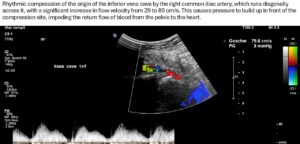

The outflow from the right pelvic hemisphere is also impaired because, as a result of the steep sacrum and significant forward tilt of the pelvis as an expression of increased lumbar lordosis, the origin of the vena cava is also pushed and compressed from the dorsal side, so that the sagittal vessel width is only 3 mm.

This leads to a significant acceleration of flow at the transition from the right common iliac vein to the vena cava from 29 to 76 cm/s.

The further course of the vena cava is unaffected, with a sagittal width of 7 mm in its initial section, a width of 17 mm in the hepatic segment, and a width of 17 mm as it passes through the diaphragm. Flow velocities range from 52 cm/s at the diaphragm to 235 cm/s at the narrowest point of the vena cava.